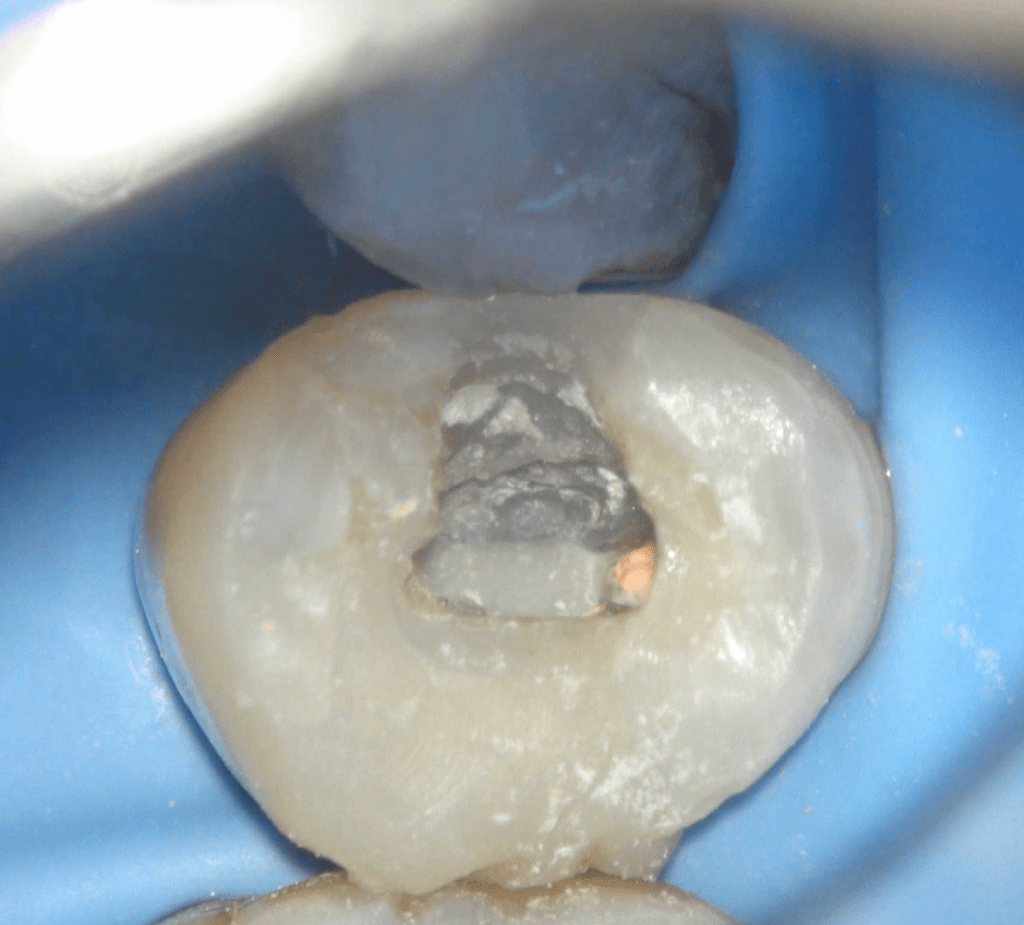

Fisura, remoción amalgama para explorar